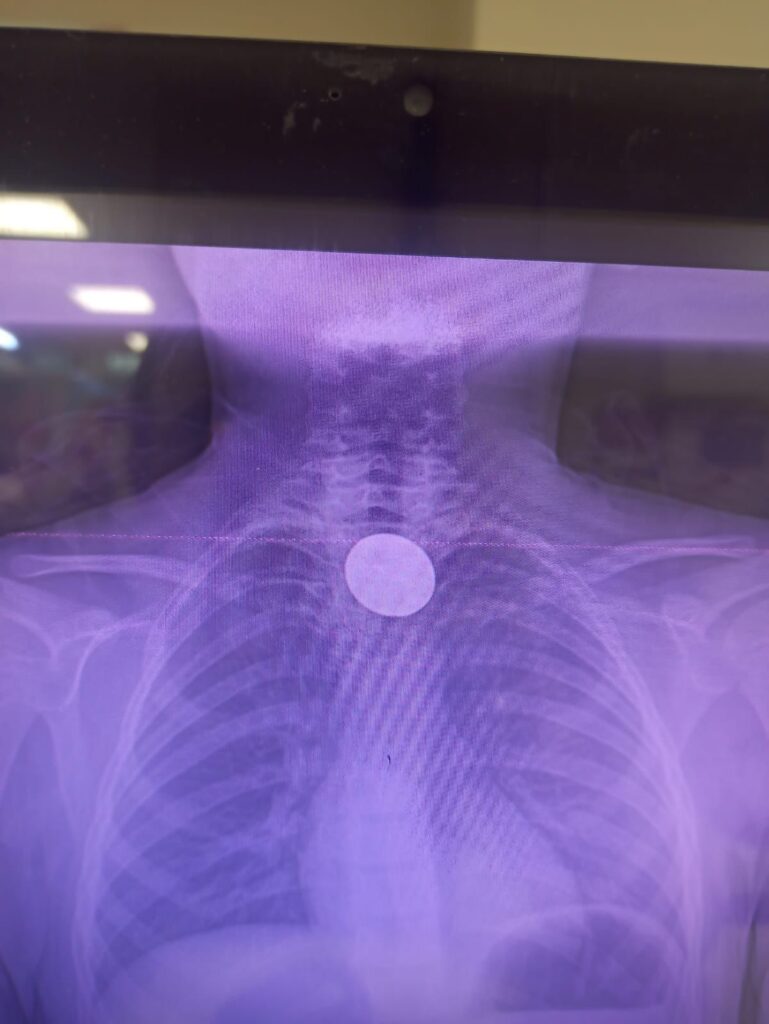

5 TL’lik madeni para yutan 8 yaşındaki Y.K., Siirt Eğitim ve Araştırma Hastanesi’nde gerçekleştirilen başarılı bir operasyonla sağlığına kavuştu.

Edinilen bilgilere göre, yabancı cisim yutma şikâyetiyle hastaneye başvuran küçük hasta, yapılan ilk değerlendirme ve görüntüleme tetkiklerinin ardından ilgili branşlar tarafından operasyona alındı. Y.K.’nin yemek borusuna kadar ilerlediği tespit edilen madeni paranın çıkarılması için Gastroenteroloji Uzmanı Dr. Yaren Dirik ile Kulak Burun Boğaz (KBB) Hekimi Dr. Yasin Gökçınar tarafından ortak bir girişim gerçekleştirildi.

Siirt Eğitim ve Araştırma Hastanesi Başhekim Yardımcısı Uzman Dr. Burak Özkan, konuya ilişkin yaptığı açıklamada çocuk hastalarda yabancı cisim yutma vakalarının ciddi riskler oluşturabileceğine dikkat çekerek, “Hastanemize başvuran 8 yaşındaki hastamızın yemek borusuna kaçan madeni para, gastroenteroloji ve KBB ekiplerimizin koordineli ve titiz çalışmasıyla herhangi bir komplikasyona yol açmadan başarılı bir şekilde çıkarılmıştır. Operasyon süreci sorunsuz geçmiş olup hastamızın genel durumu iyidir,” ifadelerini kullandı.